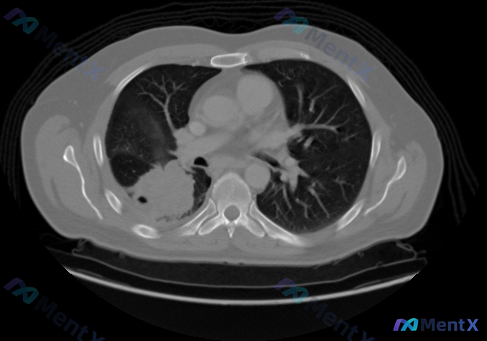

看到这份胸部CT肺窗的病例资料,整理了一下思路和大家分享讨论。 病例核心影像信息 本次提供的是胸部CT肺窗横断面影像,核心异常如下: 1. 右肺上叶病变:可见一类圆形高密度实性肿块影,边缘有明显毛刺样改变,伴浅分叶征;病灶周围可见磨玻璃密度影("晕征"表现),边缘可见支气管血管束向病灶聚拢(血管集束...